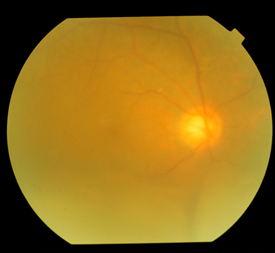

Vod 0.1,IOP 12.0mmHg,1米光定位:右上,上方,左上(-),余方向(+),晶状体后囊下混浊,玻璃体条带状混浊,眼底模糊,坐位:下方4点-8点位周边部视网膜脱离呈球形隆起;卧位:下方视网膜脱离变扁平,后极部视网膜脱离累及黄斑;颞上方远周边部可见一圆形隆起。

Vod 0.1, IOP 12.0mmHg. A superior visual field defect, subcapasular opacity of the lens, and mild vitreous opacity were noticed Fundusexamination in upright position found bullous retinal detachment at 4-8o’clock in the peripheral portion of the retina, whereas in the supine positionthe retinal detachment shifted to the posterior part of the retina involving the macular. No retinal hole was found. A protuberant lesion was noticed in the temporal-superiorquadrant of the peripheral retina.

图5 OCT:右眼黄斑色素上皮病变,神经上皮脱离

Fig5 OCT revealed RPEirregularity in the macula and retinal detachment.

图6:造影所见

右眼:FFA:动静脉充盈时间略延迟,视盘周围、后极部及黄斑周围血管弓附近可见多灶性小类圆形,条形低荧光斑,边界清晰,部分融合成片。随时间延长,低荧光斑周未见着染。视盘边界不清,颞上圆形弱荧光,边界清楚,下方网膜血管漂浮(网脱),晚期:视盘强荧光,颞上圆形弱荧光呈稍强荧光,ICGA:相应部位始终类圆形低荧光,晚期无变化。

左眼:FFA:中周可见大片斜行脉络膜褶皱,黄斑区可见片状强荧光,晚期:脉络膜褶皱不变。黄斑区强荧光片退行,ICGA黄斑区可见小片荧光遮蔽(色素堆积?)

Right eye: The dye transit was slightly retarded. There were multiple round-shaped, well demarcated hypofluorescence spots in the posterior portion of the retina, with no staining in the late phase. The margin of the optic disc wasblurred and was hyperfluorescen in the late phase. In ICGA, the hypofluorescence spots remained unchanged from the beginning to the end.

Left eye: FFA showed clusters of choroid folds in the mid-peripheral retina. Two hyperfluorescent spotsin the macular was shown in the early phase, laterthe hyperfluorescence gradually diminished.